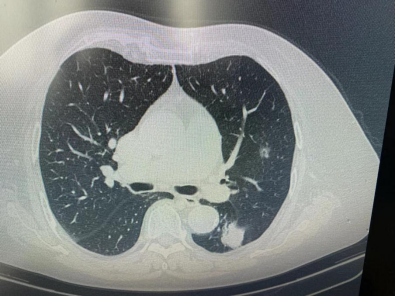

原来何奶奶的肺结节一个位于左下肺,直径约3.0cm,考虑为中期肺癌;另一个位于左上肺较深的位置,直径约1.2cm,考虑为早期肺癌,需及时手术治疗。

胸部医学中心组织多学科MDT讨论,何奶奶左下肺肿瘤较大但位于外周,可行楔形切除;而左上肺结节位置深,可行热消融治疗。最终决定实施“外科切除+热消融”结合的杂交手术。经过周密细致的术前准备,手术分为两部分开展:

第一步,徐驯宇主任团队为患者施行胸腔镜左下肺肿瘤楔形切除及淋巴结清扫,最大程度保留肺组织。

第二步,陈前顺副主任进行CT引导左上肺肿瘤热消融,整个过程仅耗时10分钟